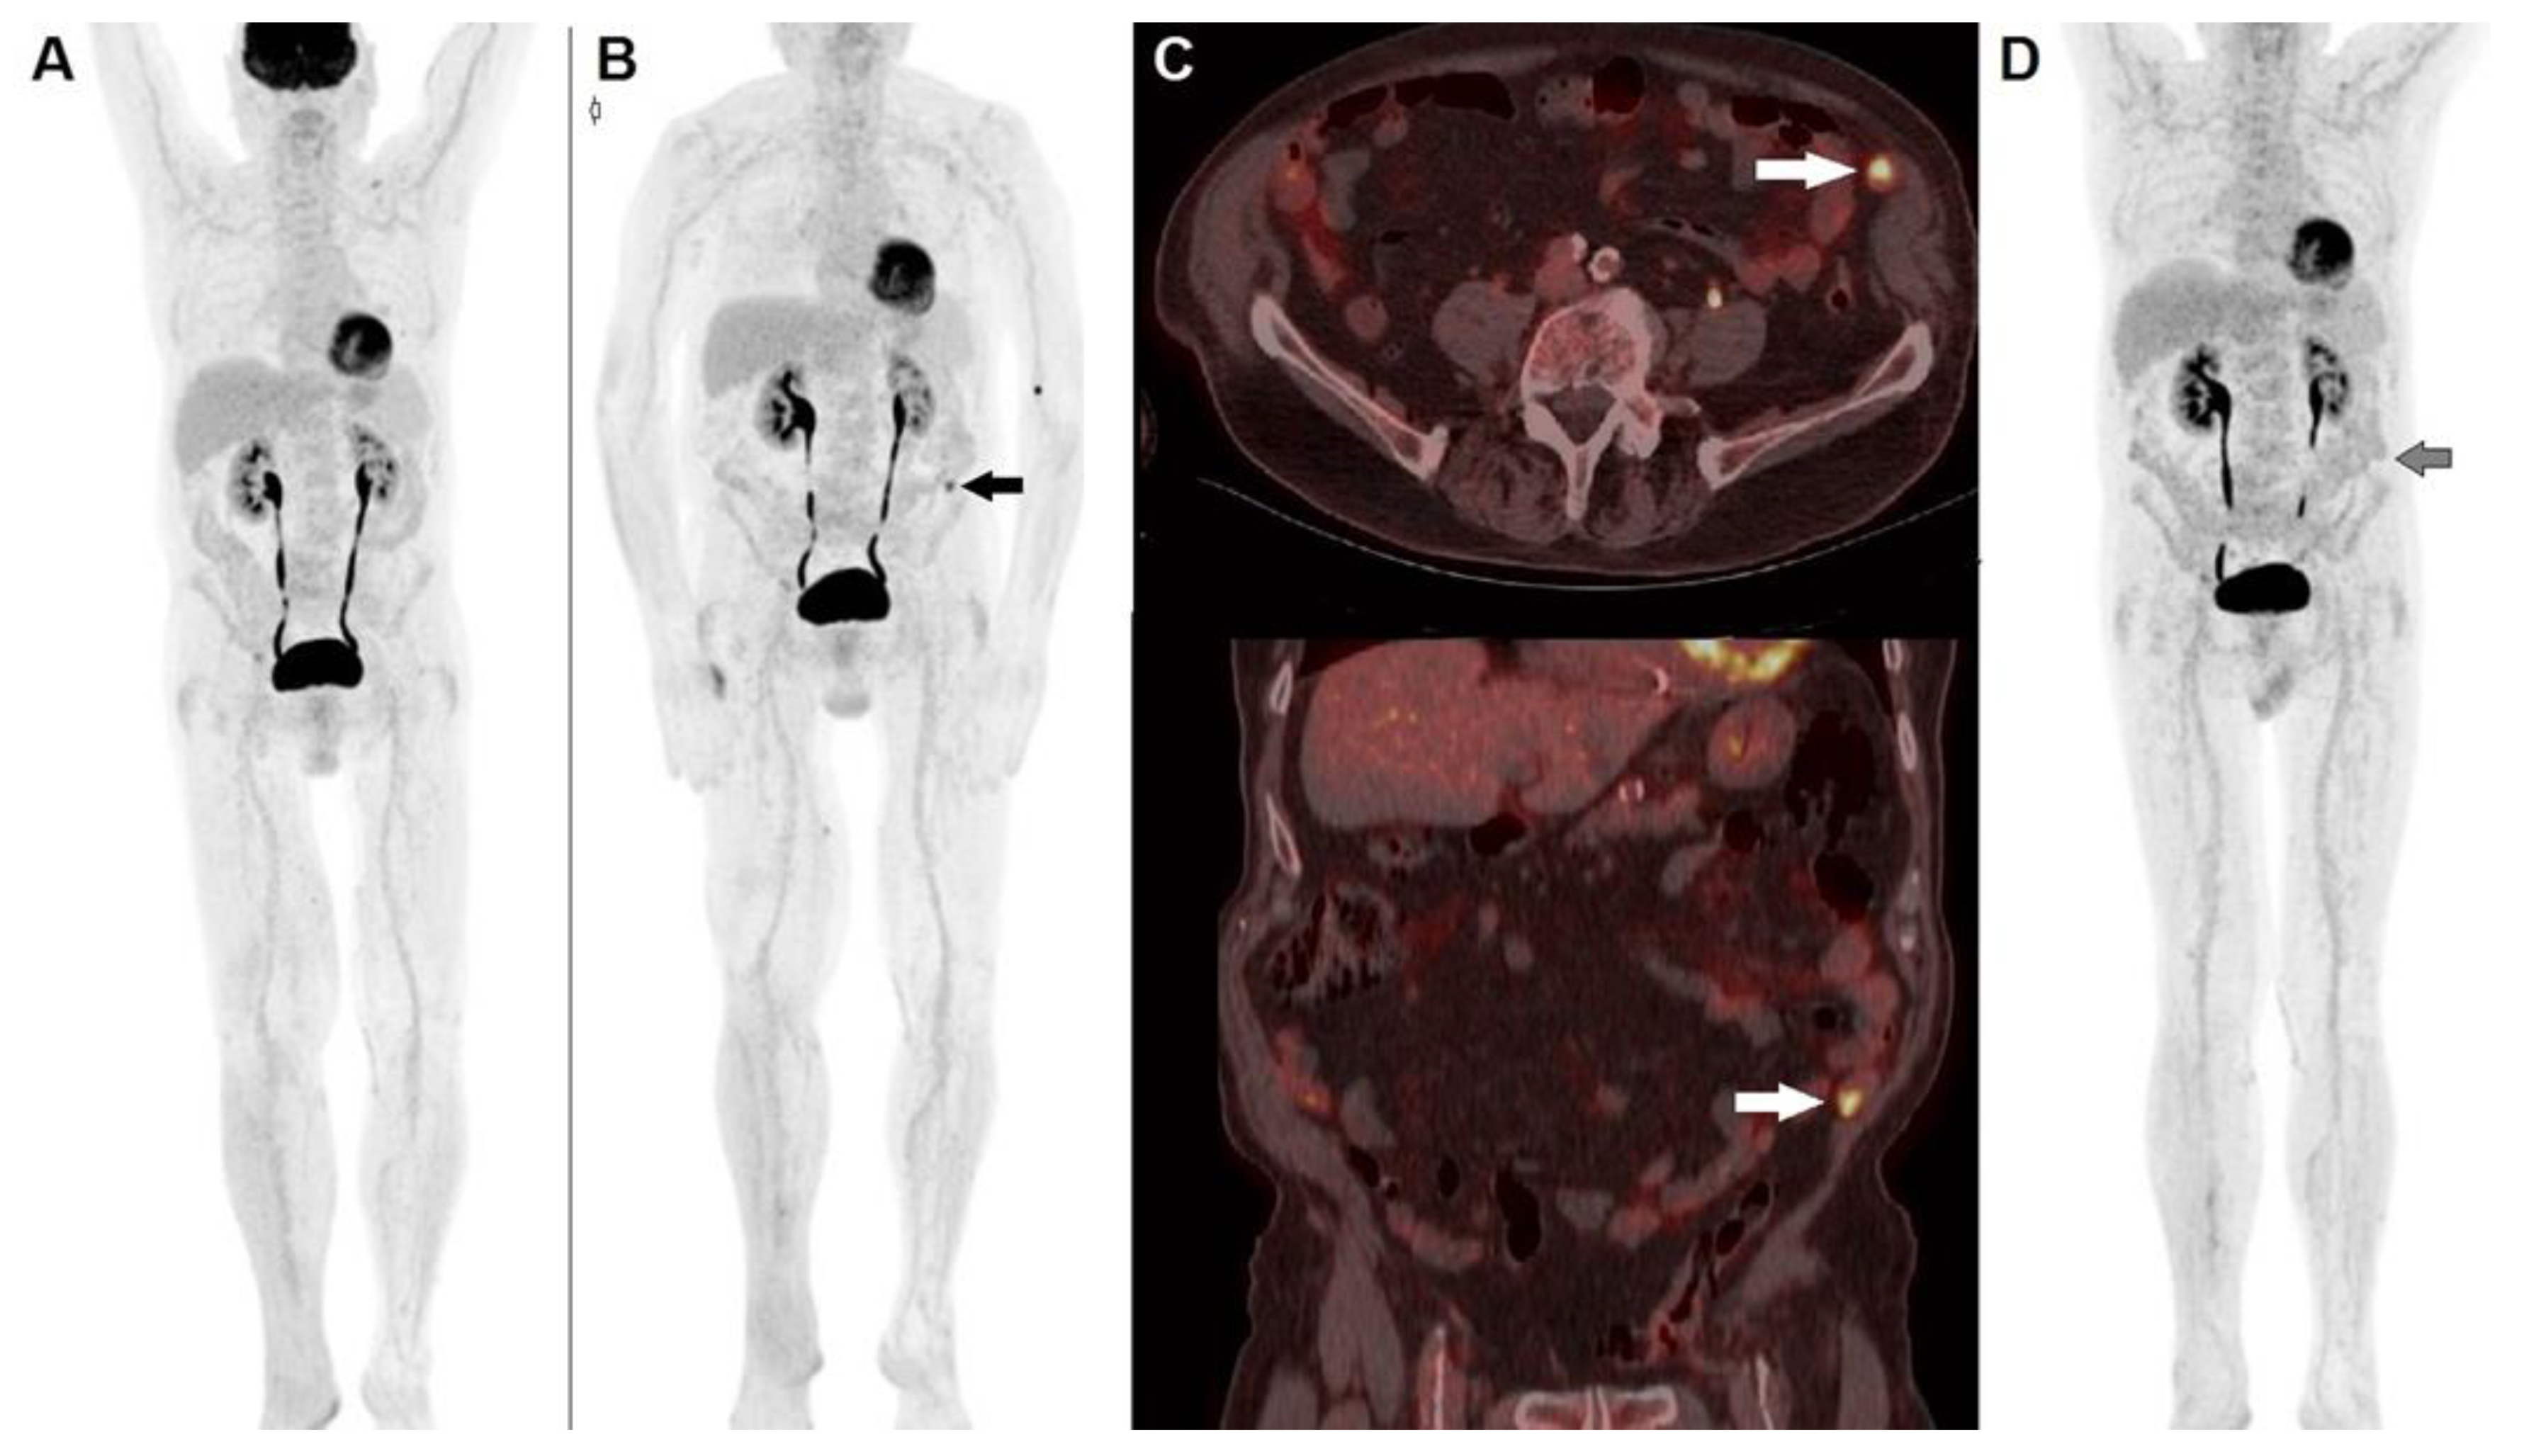

2. PET/CT with 18F-FDG for Prognostication and Staging of Malignant Melanoma

| Holtkamp et al. [22] | 2020 | Prospective, Single-center | Staging and follow-up in patients with in-transit or satellite MM metastases | n = 25 | PET/CT upstaged 4 out of 25 patients (16%) therefore leading to a change in clinical management. Furthermore, PET/CT detected the onset of distant metastases during follow-up in 10 cases within 6 months from diagnosis. |